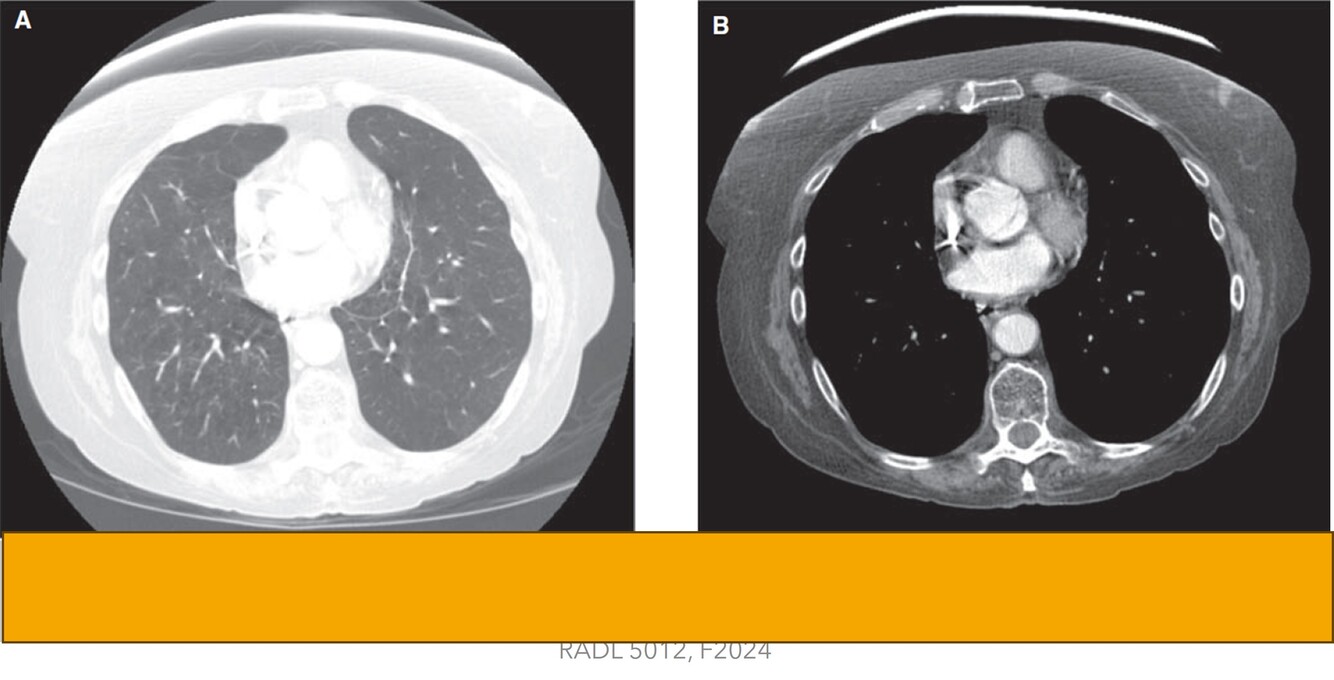

What window settings are seen in images A and B?

A=Lung window

B=Mediastinal window

Can’t get a complete picture without seeing these two window

-Detail of the lung parenchyma seen

-Limitations=can’t appreciate mediastinal structures

How well did you know this?

1

Not at all

2

3

4

5

Perfectly

21

Q